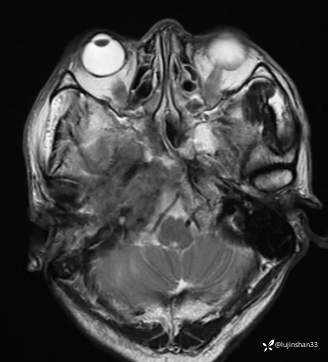

(2023-06-02 11:09,本院)磁共振(颅脑):1、右侧颞骨全切除术后改变,术区及相邻右侧斜坡、颞肌、咬肌、翼内外肌异常信号,考虑炎性肉芽肿性病变可能,请结合临床随诊复查;2、右侧小脑半球异常信号,考虑炎性病变可能;3、脑内散在缺血灶,软化灶形成;4、双侧蝶窦炎。

(2023-05-29 16:07,本院)CT颅脑:1、右侧颞骨全切除术后改变,术区见气体密度影,瘘管形成可能;术区多发软组织影,不完全除外炎性改变可能。2、左侧颞骨CT平扫未见明显异常。